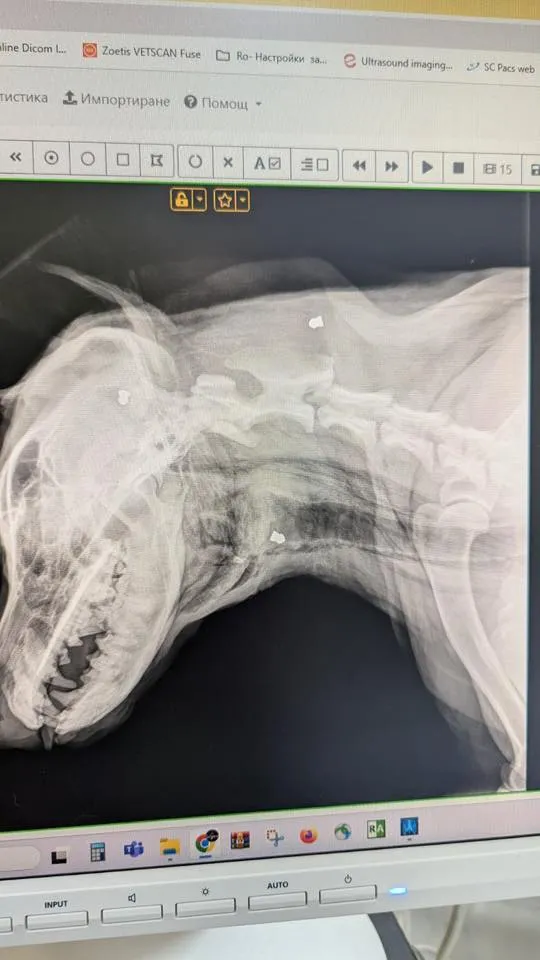

Животното е било транспортирано по спешност в ветеринарна клиника, където лекарите установяват осем прострелни рани от въздушна пушка – една от тях в окото и друга в трахеята. Последната е застрашавала живота ѝ и се е наложила незабавна операция.

Само за първия ден сумата за лечението, операцията и прегледите е достигнала 1600 лв., а предстоят още сериозни разходи – медикаменти, контролни изследвания, рентгенови снимки, престой в клиниката и рехабилитация.